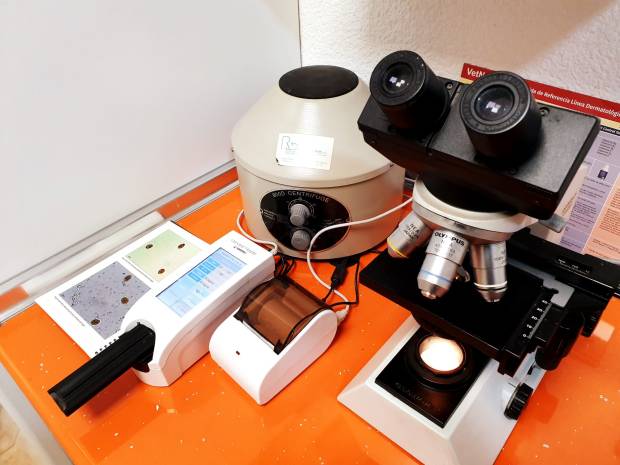

Otros los podemos realizar en la propia clínica, para lo que contamos con un área de análisis.